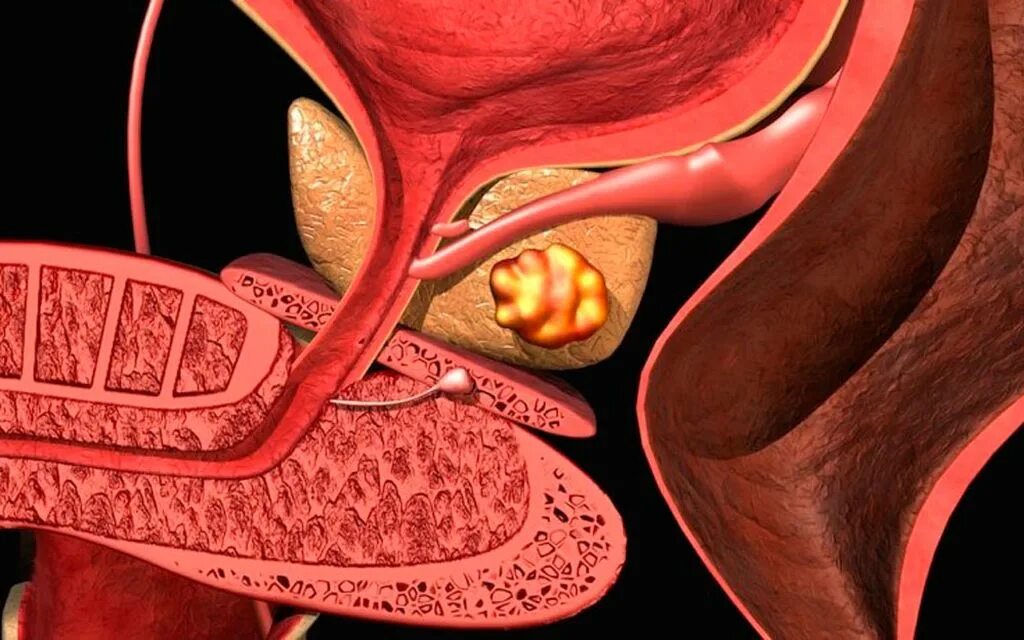

Анатомия аденомы предстательной железы. Эктопия предстательной железы. Злокачественная опухоль предстательной железы. Злокачественная аденома предстательной железы

Анатомия аденомы предстательной железы. Эктопия предстательной железы. Злокачественная опухоль предстательной железы. Злокачественная аденома предстательной железы Карцинома 4 степени предстательной железы. Онкология предстательной железы. Опухоль предстательной железы стадии

Злокачественные новообразования простаты. Злокачественная опухоль предстательной железы в пожилом возрасте. Новообразования простаты злокачественной природы Сосудисто нервный пучок предстательной железы. Экстракапсулярная экстензия предстательной железы что это. Лучевая диагностика предстательной железы. Инвазия капсулы предстательной железы

Сосудисто нервный пучок предстательной железы. Экстракапсулярная экстензия предстательной железы что это. Лучевая диагностика предстательной железы. Инвазия капсулы предстательной железы Предстательная железа у мужчин. Представительна яжелеза. Опухальпредседательнойжелезы